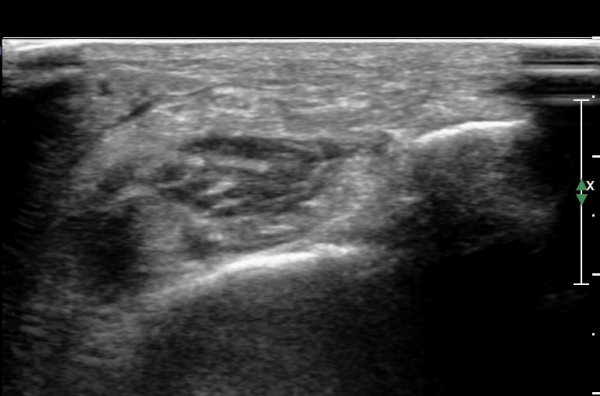

¾Æ·§´Ù¸® ¿ÜÃø Ⱦ´Ü¸é°Ë»ç¿¡¼ Àåºñ°ñ±Ù°ú ¹ß°¡¶ô½ÅÀü±Ù »çÀÌ¿¡¼ õºñ°ñ½Å°æÀÌ Á¤»óÀûÀ¸·Î °üÂûµÈ´Ù(»çÁø 1, , 2, 3, 4, 5).